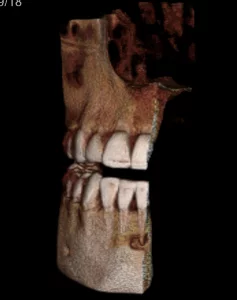

A CBCT was taken after a negative cold test indicated a necrotic tooth.  When the CBCT was taken, we could clearly see that the abscess had completely perforated the labial bone at the apex of #24 and was close to doing so on #25.

As we investigated more deeply, we identified another critical piece of information that would affect our treatment plan: a second canal on #24.

Had I initiated treatment on this particular tooth and kept my access very conservative, there’s a chance I would have missed the other canal. Furthermore, had I started the treatment and then found the second canal after access into the chamber, I would have had to spend time determining the anatomy of both canals.  For example, I would have had to determine if they had separate apicies.